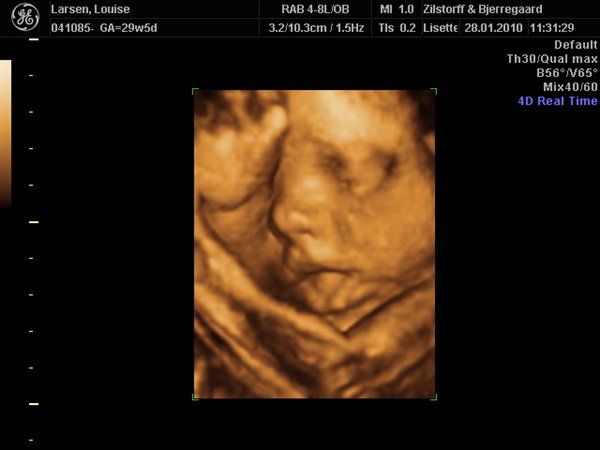

Vi har været afsted, og vi fik afvide at man anbefaler uge 29. Der er babyen stor nok til at kan se ansigts træk osv, men den er stadig så lille at der er meget fostervand rundt om babyen, hvilket er vigtig for billedernes kvalitet.... Så uge 29! Kan lige sætte et billede ind her fra vores 3d scanning i uge 29...

Zilstorff & Bjerregaard og deres klinik ligger i silkeborg, de er smadder søde og rigtig dygtige....

Vedhæftede fotos (klik for at se i fuld størrelse)